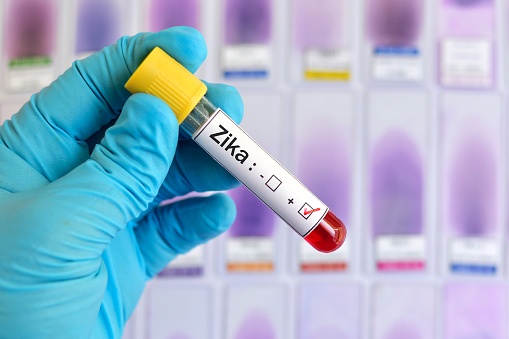

Zika virus infection intensified due to dengue antibodies presence, preliminary research suggests

Zika virus infection intensified due to dengue antibodies presence, according to preliminary research. There are four serotypes (strains) of dengue virus, and infection with one of the serotypes generally leads to a self-resolving disease. To answer the question of whether dengue virus could impact Zika virus, the researchers used two broadly neutralizing anti-dengue virus monoclonal ...click here to read more